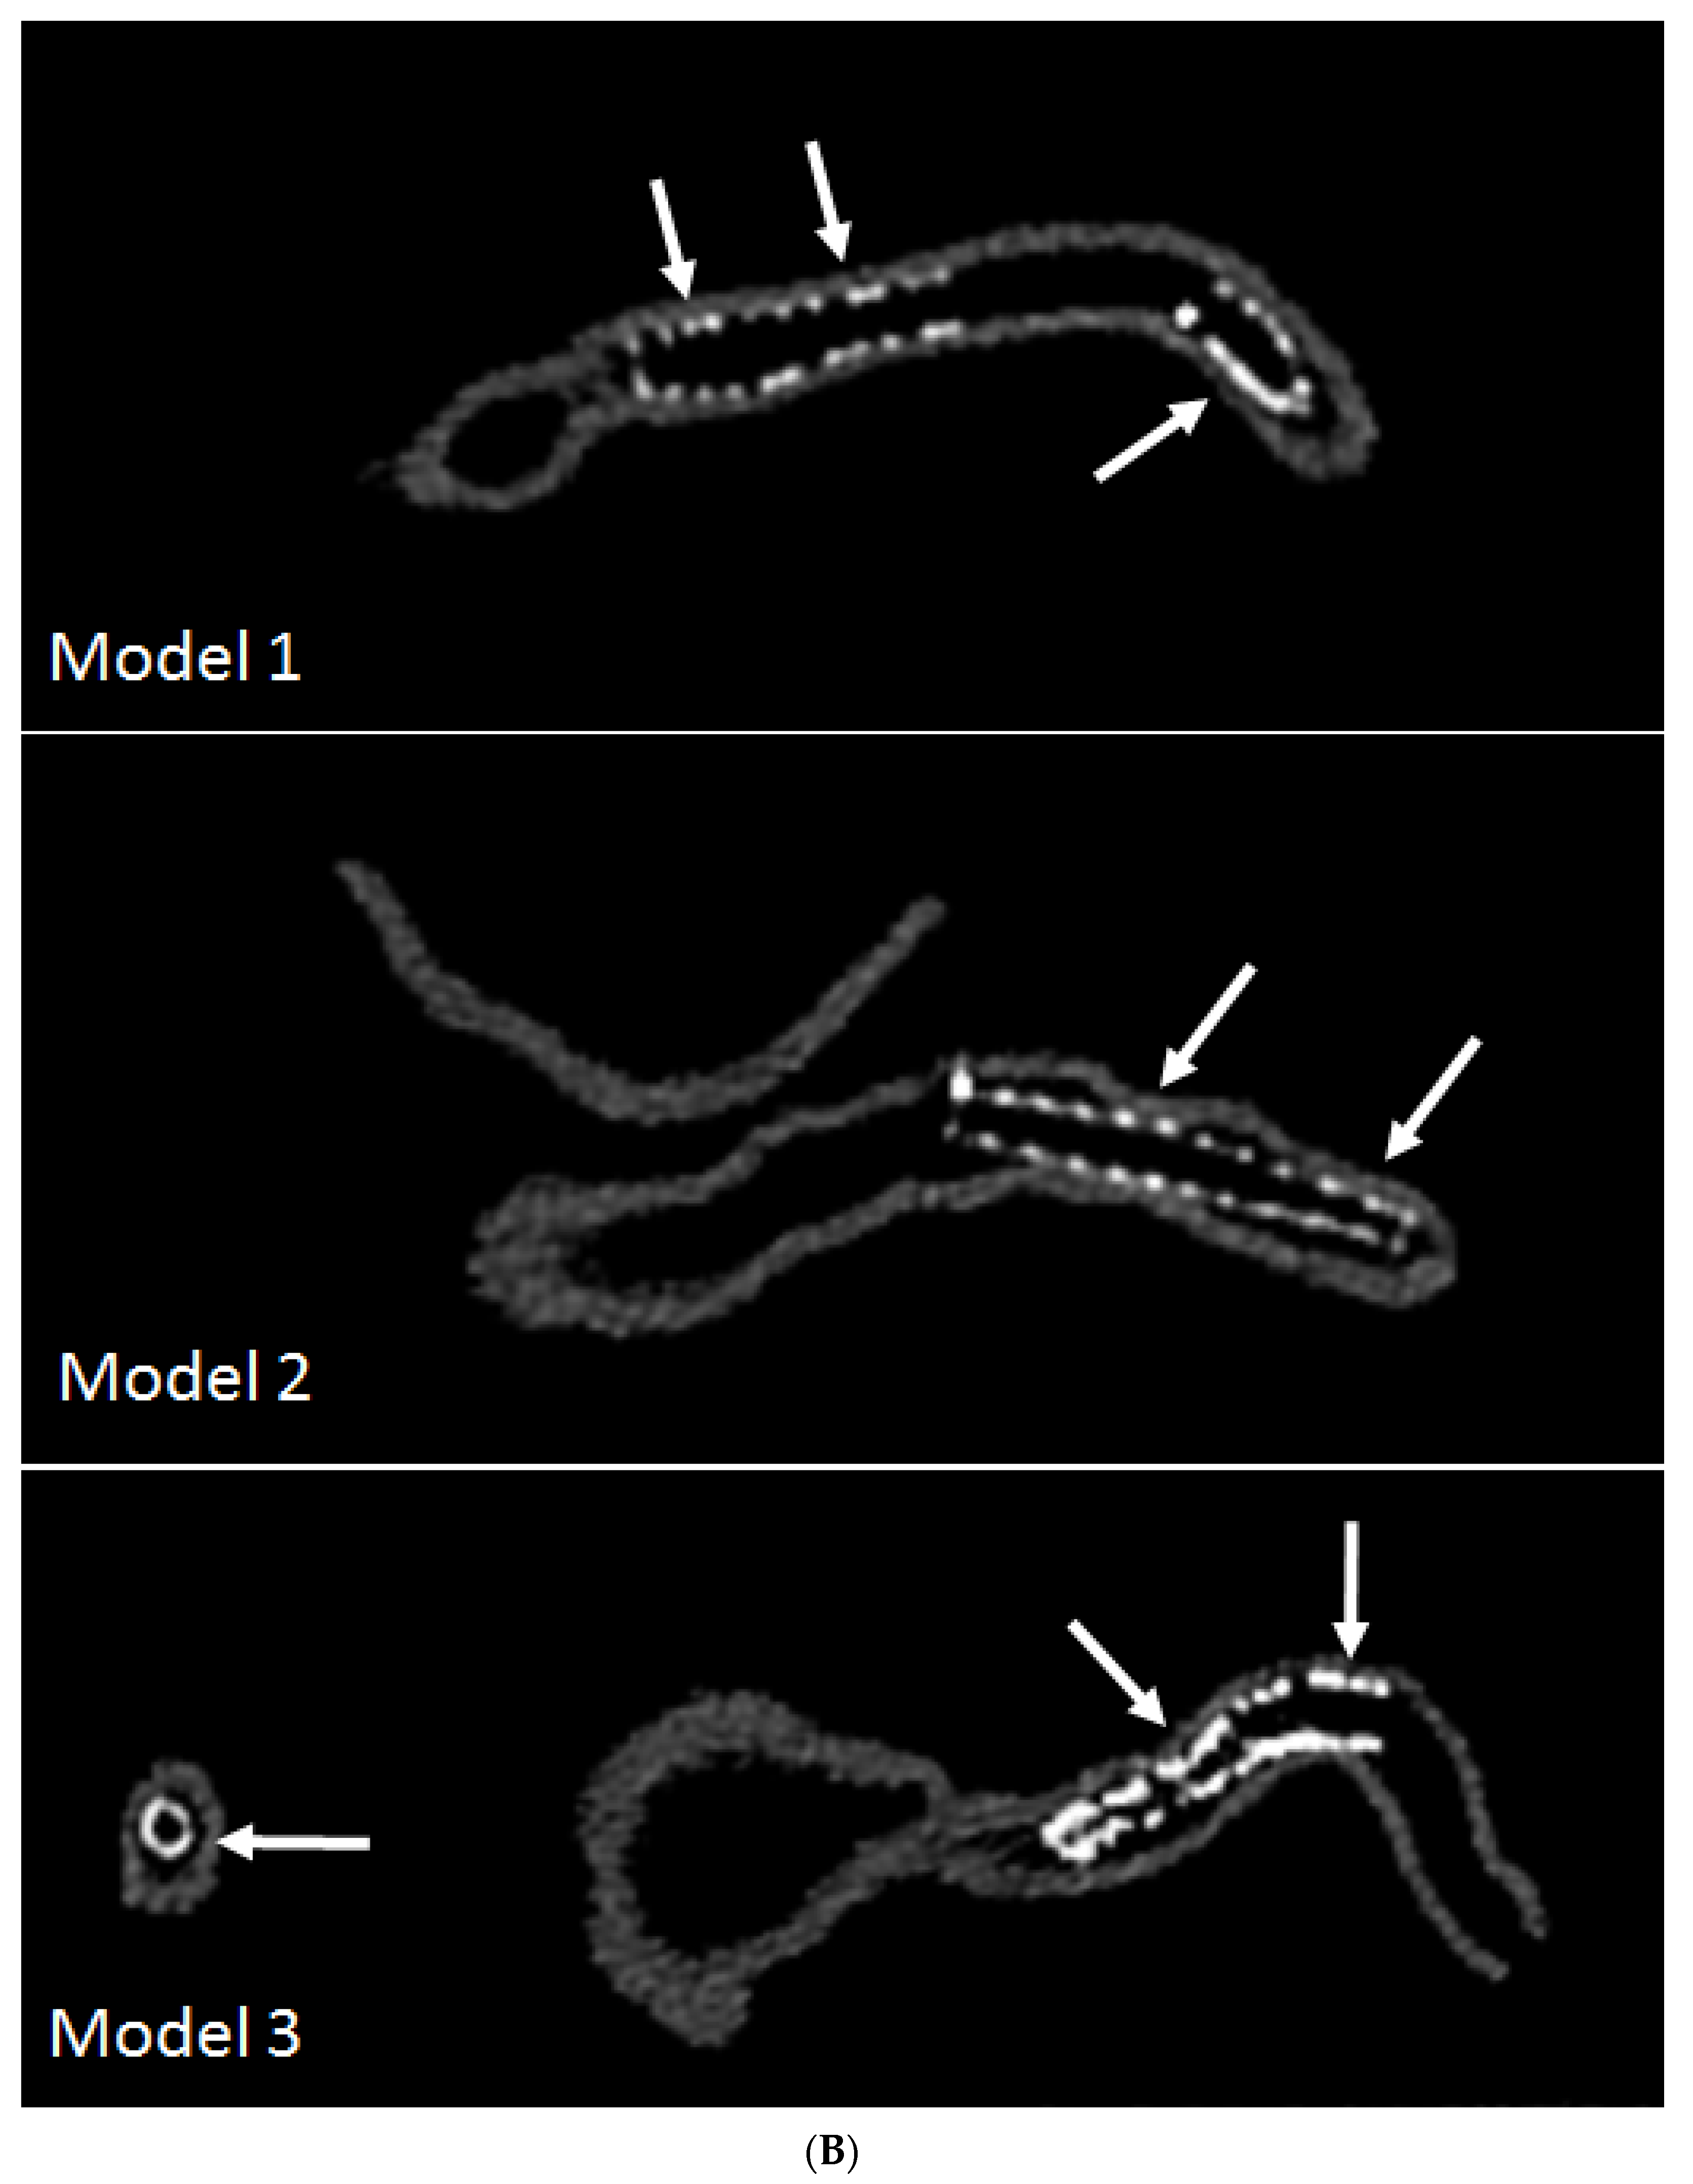

- Sun, Z.; Ng, C.K.; Squelch, A. Synchrotron radiation computed tomography assessment of calcified plaques and coronary stenosis with different slice thicknesses and beam energies on 3D printed coronary models. Quant. Imaging Med. Surg. 2019, 9, 6–22. [Google Scholar] [CrossRef] [PubMed]

- Sun, Z. 3D printed coronary models offer new opportunities for developing optimal coronary CT angiography protocols in imaging coronary stents. Quant. Imaging Med. Surg. 2019, 9, 1350–1355. [Google Scholar] [CrossRef] [PubMed]

- Sun, Z.; Jansen, S. Personalized 3D printed coronary models in coronary stenting. Quant. Imaging Med. Surg. 2019, 9, 1356–1367. [Google Scholar] [CrossRef] [PubMed]